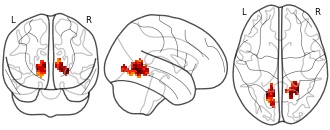

"name": "Multi_VBMsmaller_fMRIenhanced",

"description": "Multi-modal analysis in BPD. Brain regions exhibiting smaller gray matter and enhanced activation during emotion processing in BPD compared to healthy controls. Note: Results were thresholded at p<.0025. Note2: Results were updated (see Erratum for this publication).",